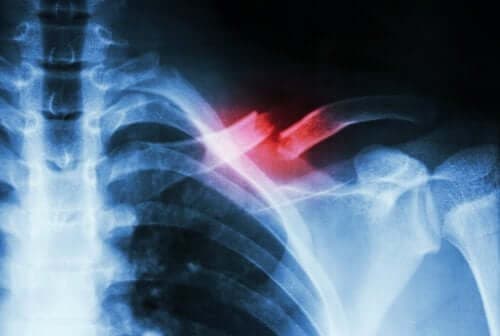

Acest tip de fractură este dificil de diagnosticat. Pacientul trebuie să consult un medic, care îl va supune unor teste complementare pentru a diferenția această problemă de alte afecțiuni. Din păcate, fracturile de stres pot fi detectate rareori cu ajutorul radiografiilor.

Dacă țesutul osos nu prezintă continuitate, putem spune că avem de-a face cu o fractură. Majoritatea fracturilor au drept cauză loviturile sau traumatismele. Însă cele de stres sunt consecința slăbiciunii sau oboselii. Prima problemă survine atunci când există carențe nutritive, pe când cea de-a doua implică abuzarea continuă a mușchilor prin mișcări repetitive sau activități suprasolicitante.

Fracturile de stres sunt asemenea unor crăpături care se formează la nivelul osului. Așa cum am menționat anterior, principalele lor cauze sunt microtraumatismele repetate sau suprasolicitarea. Acestea pot cauza durere extremă atunci când pacientul execută anumite activități fizice – durere care dispare adesea odată cu încheierea activității fizice.